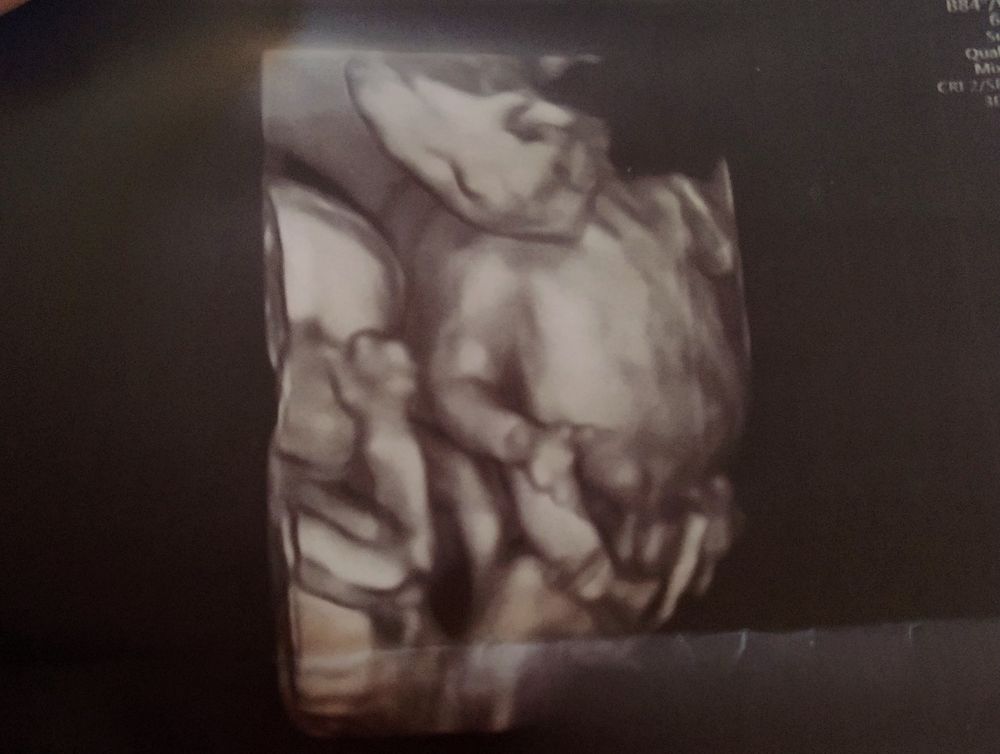

Можно, вот такой братский портрет в 18 недель. Изображение

24.07.2022